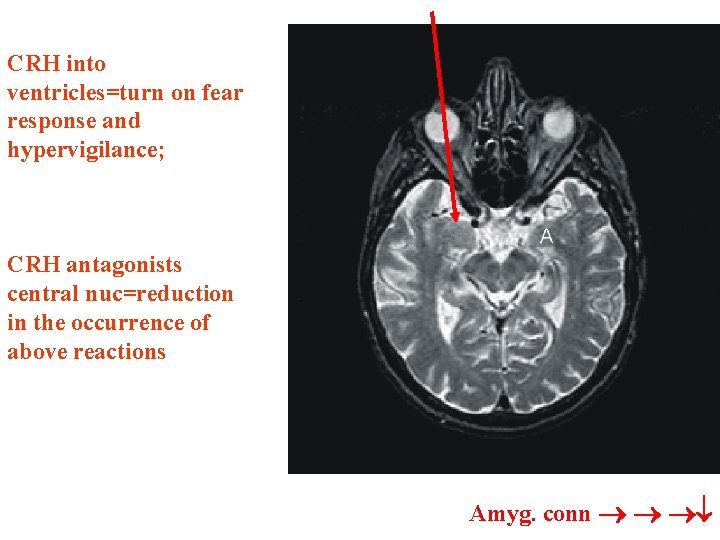

SENSORY inputs to LATERAL NUCLEUS; then relayed to basal, and accessory basal to reach: CENTRAL NUC =OUTPUT CRH receptors on cells and uses CRH as transmitter to LC adrenal medulla via pregang. sym. CRH ventricles

CRH into severe ventricles=turn on fear response and hypervigilance; CRH antagonists central nuc=reduction in the occurrence of above reactions • Target CRHCRH Amyg. conn